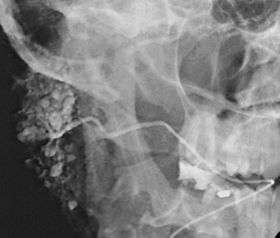

![]() Sialogram in a patient suspected of Sjögren's syndrome | |

This study is interpreted by evaluating the morphology of the salivary ducts for obstructions and chronic inflammation. Sialodochitis is a term describing dilation of the ducts caused by repeated inflammatory or infective processes. There is also irregular salivary duct stricture (narrowing) of the duct, which creates an appearance known as "sausage link" pattern on a sialogram. Suggestions of abscesses and autoimmune diseases such as Sjögren syndrome can also be elicited. Sialadenitis is inflammation of the salivary glands, which may cause acinar atrophy and create an appearance known as "pruning of the tree" on a sialogram, where there are less branches visible from the duct system. A space occupying lesion that occurs within or adjacent to a salivary gland can displace the normal anatomy of the gland. This may create an appearance known as "ball in hand" on an sialogram, where the ducts are curved around the mass of the lesion.[3]